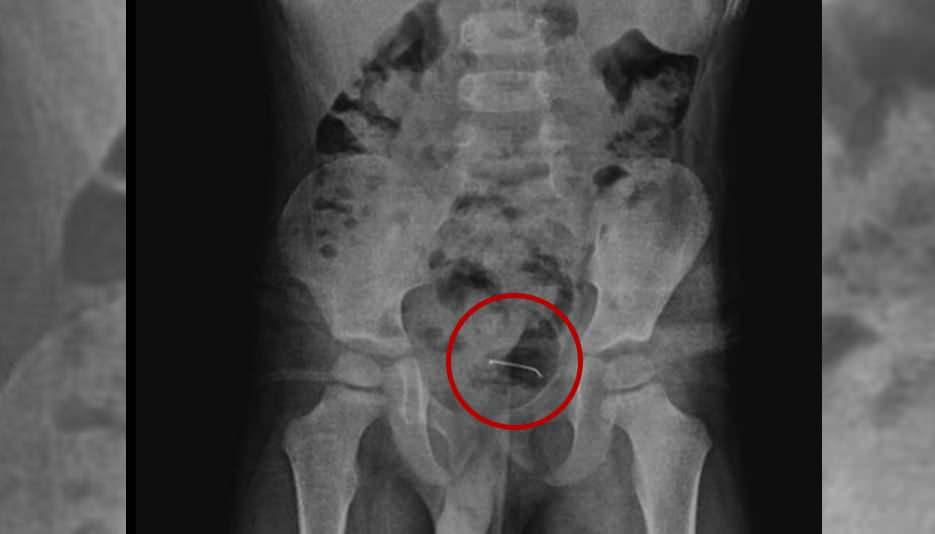

Bitlis’te oyun oynarken toplu iğne yutan 5 yaşındaki çocuk “yabancı husus yutma” münasebeti ile ailesi tarafından hastaneye götürüldü. Tabiplerin incelemelerine karşın sonuç alamayan aile meskene geri döndü. 9 ay sonra şiddetli karın ağrısı yaşayan çocuk tekrar hastaneye götürüldü. Yapılan tetkikler sonucunda çocuğun mesane duvarında görülen ve toplu iğne olduğu tespit edilen yabancı husus başarılı bir cerrahi operasyonla alındı.

5 yaşındaki çocuğa yapılan tetkikler sonucunda, şiddetli karın ağrısına neden olan durumun mesane duvarına yapışan yabancı unsur olduğu tespit edildi. Küçük çocuğun yuttuğu 3 santimetre uzunluğundaki toplu iğne başarılı bir operasyonla alındı.

Kamçı, yabancı cismin bedenden olağan yollarla atılamadığını belirterek, “Bunun üzerine ameliyat kararı aldık. Ameliyatta cismin mesane duvarına yapıştığını gördük. Cerrahi operasyonla 3 santimetre civarındaki toplu iğneyi çıkardık. Hastayı birkaç gün takipte tuttuk. Genel sıhhat durumu düzgün olan hastamızı taburcu ettik.” ifadelerini kullandı.